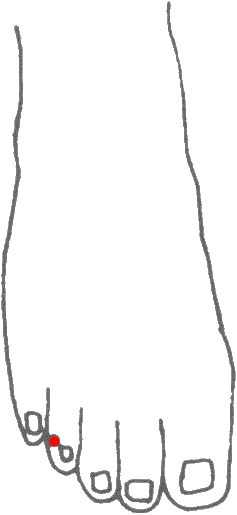

標準定位:足竅陰穴在足第4趾末節外側,距趾甲角0.1寸(指寸)[4]。

足竅陰穴位於足趾,第四趾末節外側,趾甲根角側後方0.1寸(指寸),伸足取穴[4]。

足竅陰穴在趾端的位置

足竅陰穴在趾端的位置

9 足竅陰穴的取法

足竅陰穴位於足趾,第四趾末節外側,趾甲根角側後方0.1寸(指寸)。伸足取穴。[5]

仰臥或垂足,在足第4趾趾甲根角側後方0.1寸處取穴;或於足第4趾外側甲根角側後方(即沿角平分線方向)0.1寸,相當於沿爪甲外側畫一直線與爪甲基底緣水平線交點處取穴[6]。